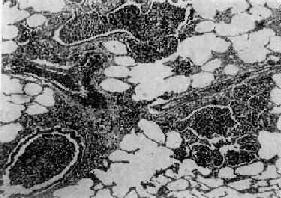

图9-19 支气管肺炎

图中见灶状实变的肺组织,肺泡内充满以中性粒细胞为主的炎性渗出物;病灶中有发炎的细支气管